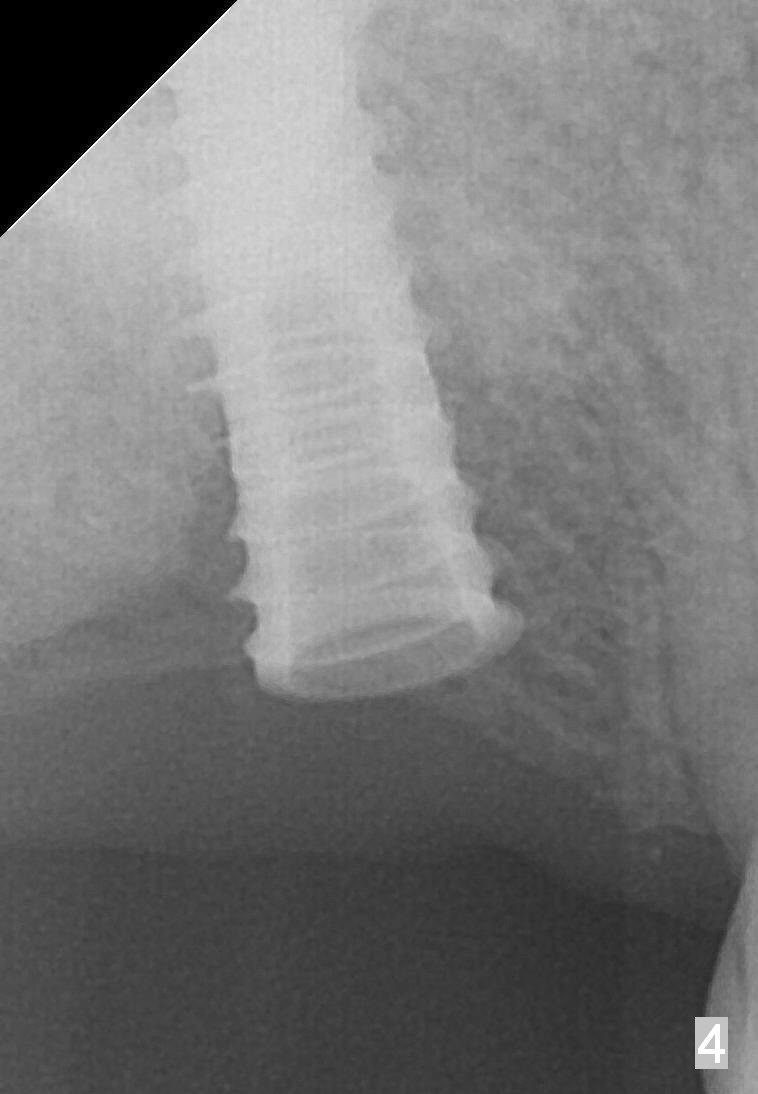

The edentulous ridge at the site of #2 is wide. Magic split is used to gain access, test bone density and start osteotomy for 9 mm (gingival level). A 1.6 mm drill is used to extend the osteotomy for depth of 13 mm. The osteotomy position and trajectory is confirmed with a parallel pin (Fig.1), which is ideal. The remaining osteotomy is finished with Magic Expanders from 3 to 4.3 mm for 15 mm. The trajectory is confirmed again with insertion of a 4.5x11 mm dummy implant at the depth of 15 mm (Fig.2). When a definitive IBS implant (5x13 mm) is placed with insertion torque >45 Ncm, the distal coronal end is not subcrestal (Fig.3-5). As the implant is placed deeper, it started to lose primary stability. When a pair abutment is placed, it keeps turning. Finally a healing abutment (6x3 mm) is placed unstable. In brief, taking several X-ray films help control osteotomy and implant position and trajectory. The implant is unstable 7 months postop (Fig.6). With local anesthesia, the implant is placed deeper by 1 mm with apparent increase in torque and a 6x4 healing abutment placed. The implant is stable 11 months postop. With 5.5x4(4) mm abutment placed, impression is taken. PA and BW will be taken after cementation of the crown. There is no bone loss 9 months post cementation (Fig.7). Return to Upper Molar Immediate Implant, 18-20, 29,30 Xin Wei, DDS, PhD, MS 1st edition 01/09/2017, last revision 08/15/2021